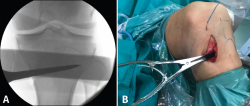

Figura 1. A: colocación del paciente con rodilla a 90° de flexión. Se marca la incisión de aproximadamente 4-6 cm que servirá para la extracción de los isquiotibiales y la osteotomía tibial alta; B: extracción de isquiotibiales para realizar la plastia.

Se marca sobre la piel la línea de incisión de 4-6 cm en la cara medial de la tibia proximal, aproximadamente 1,5 a 2 cm por debajo de la interlínea articular (Figura 1A). Una de las ventajas de esta osteotomía es que no precisa disecar e inestabilizar el ligamento colateral medial (LCM). El corte se realiza entre las dos inserciones del LCM y la placa se coloca por encima de este ligamento. De esta manera, la rodilla sigue estable aunque se decida realizar una retirada de la placa una vez consolidada la osteotomía.

Figura 2. Colocación de aguja guía: punto de entrada en la unión metafisodiafisaria tibial dirigida hacia la cabeza del peroné.

Una vez disecado el plano subcutáneo, se identifica la pata de ganso y se extraen los isquiotibiales según la técnica habitual de cada cirujano (Figura 1B). Bajo control radioscópico, se coloca la aguja guía aproximadamente medio centímetro por encima de la pata de ganso orientada hacia la cabeza del peroné, según la técnica clásica de osteotomía biplanar (Figura 2). Se marcan los cortes de la osteotomía biplanar y se realiza primero el corte vertical por encima de la tuberosidad tibial, con una inclinación de aproximadamente 120° respecto a la osteotomía de apertura llegando hasta la cortical lateral (Figura 3).